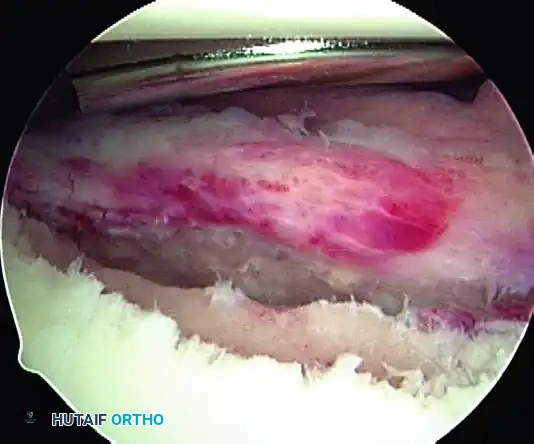

5. Recreating the Anterior Bumper

Proceed superiorly, placing the second and third double-loaded anchors. Firmly secure the sutures, compressing the capsuloligamentous complex to the abraded bone surface. This "loop and knot fixation" rolls the tissue up onto the glenoid face, recreating a robust anterior soft-tissue bumper.

D, Knots tied re-creating soft tissue bumper.

B, Restored anterior labral bumper (arthroscopic view).

C, Restored anterior labral bumper (alternate angle).

Final Construct Verification

Evaluate the final repair. The drive-through sign should be eliminated, the humeral head should be centered on the glenoid, and a prominent anterior bumper should be visible.